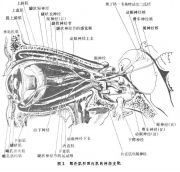

| 2021年7月26日 (一) 20:03 | 眼外肌和眼内肌的神经支配.jpg (文件) |  |

75 KB | Uploaded with SimpleBatchUpload | 3 |